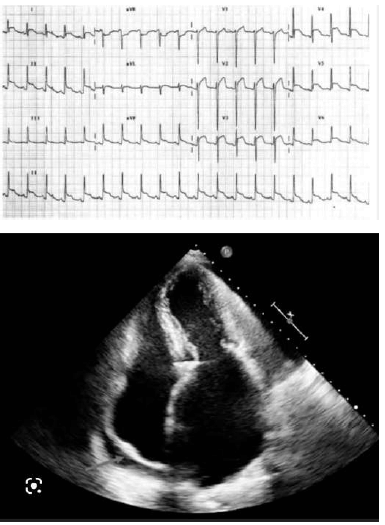

Um homem de 32 anos de idade, sem comorbidades, vem apresentando, há 6 dias, quadro de tosse seca, dor torácica que piora ao tossir e ao deitar, mialgia, palpitações, dispneia aos moderados esforços, afebril, estertores crepitantes em bases pulmonares. Apresenta pressão arterial de 92 x 48 mmHg, frequência cardíaca de 85 bpm, frequência respiratória de 22 ipm e saturação de oxigênio de 92% (ar ambiente). Realizou exames laboratoriais que evidenciaram os seguintes resultados: Hb = 14,5 g/dL; Ht = 43%; leucócitos = 6.500/mm3 (segmentados = 72%); linfócitos = 10%); plaquetas = 250.000/mm3; PCR = 4,5 mg/dL (VR < 1,0 mg/dL); DHL = 450 U/L (VR < 220 U/L); troponina = 45 ng/L (VR < 14 ng/L); creatinina = 1,1 mg/dL (VR < 1,2 mg/dL); ureia = 84 mg/dL (VR: 10 a 50 mg/dL); sódio = 138 mmol/L (VR = 135 a 145 mmol/L); potássio = 4,1 mmol/L (VR = 3,5 a 5,0 mmol/L). A tomografia de tórax revelou opacidades em vidro fosco acometendo 25% do parênquima pulmonar e discreto derrame pleural bilateral. A seguir, são apresentados os resultados do ECG e o ecocardiograma realizados.

Com base nas informações apresentadas nesse caso clínico, assinale a alternativa que indica a principal hipótese diagnóstica cardiológica do paciente.